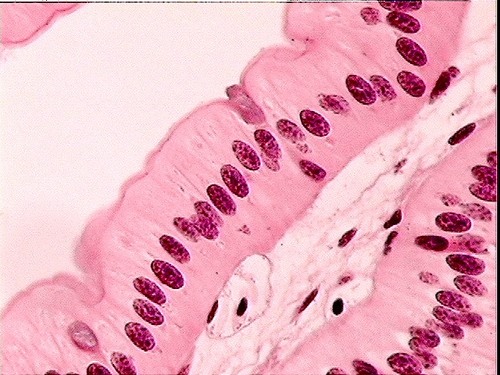

simple columnar

single layer of elongated cells; functions in protection and absorption